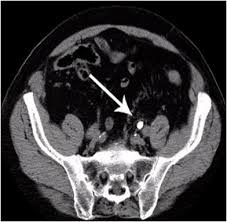

- 초음파·CT(결석·출혈 원인)